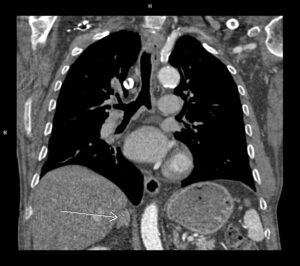

Figura 1: reconstructie oblic axială in 4 camere

Discuţie caz nr 90: se evidențiază o soluție de continuitate la nivelul septului interventricular în treimea medie cu diametrul de 0.2 cm ce este restricționat de trabecule ventriculare drepte și de crista supraventricularis. La acest pacient a fost descoperire întâmplătoare, indicația de efectuare a examinării cardioCT era boală coronariana cronică.

DE LUAT ACASĂ!!! Un defect de sept interventricular mic, restricționat de trabeculele VSD, este un tip de VSD în care defectul este blocat parțial sau complet de fibrele musculare și crestele din ventriculul drept, limitând fluxul de sânge prin DSV și reducând potențial severitatea shuntului. Pentru evidențierea suntului este utilă completarea cu examinare cardio-RM pentru calcularea raportului Qp : Qs prin hărți de velocitate.